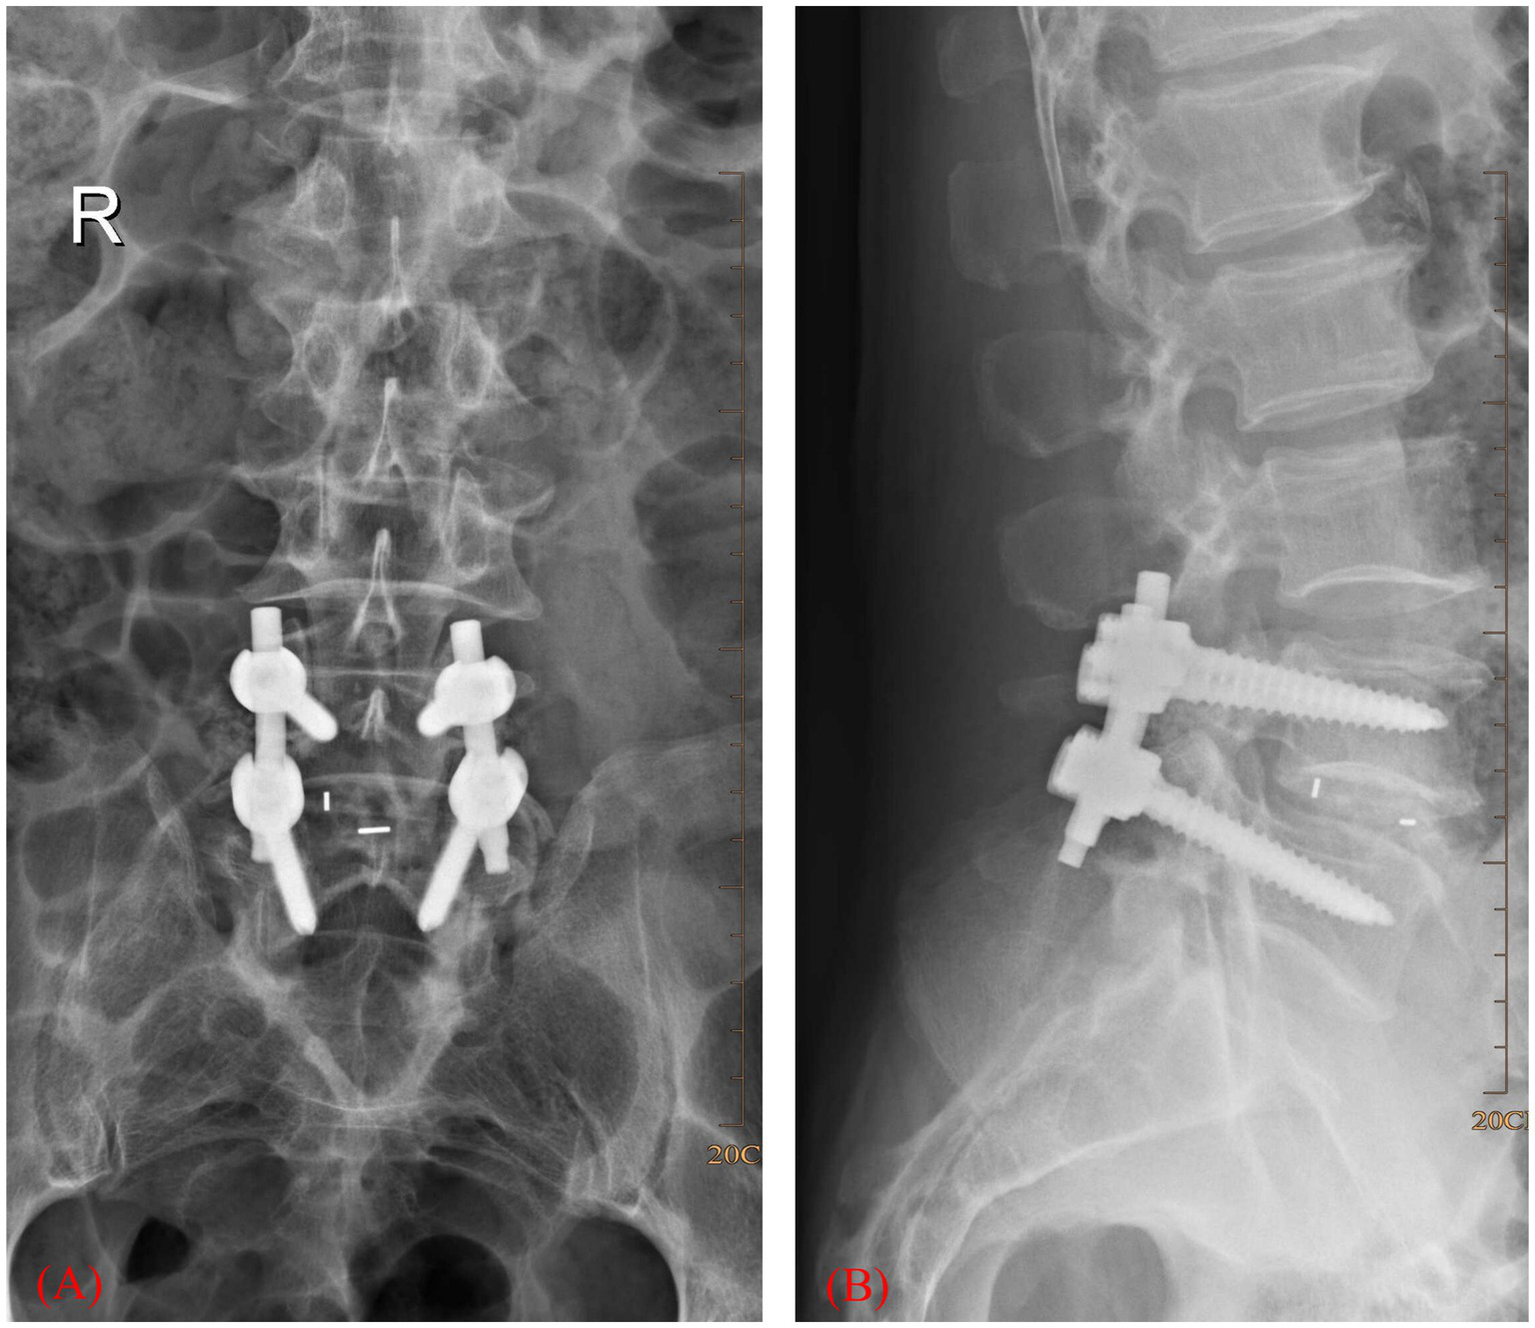

Medical records of elderly patients (aged ≥65 years) who underwent surgery because of lumbar spinal stenosis between July 2016 and July 2018 were collected. Figure 1 is a scheme showing the process of enrolling the patients in our study. Finally, 168 patients were recruited in our study, 84 in the intervention group and another 84 in the control group. There were 103 males and 65 females. The age was 68 ± 3 years on average. Figure 2 shows a postoperative X-ray image of the spine after the lumbar fusion surgery. The inclusion criteria for the patients in our study are listed as follows. 1. Patients underwent lumbar spinal fusion surgery; 2. no history of trauma or operation on the lower limbs; 3. no neuromuscular or cerebral infarction disease history; 4. no cancer or bone destruction diseases; 5. muscle strength of preoperative lower limbs was grade IV or grade V; 6. no preoperative lower-limb DVT; 7. no infection after surgery; 8. no nerve injury was observed. Patients that did not apply to these criteria were excluded from this study.

Figure 2

X-ray image showing lumbar interbody fusion surgery. (A) Coronary plane. (B) Sagittal plane.